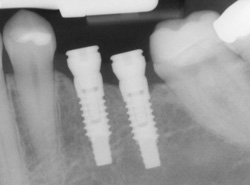

Dental implants are used as an option to replace missing teeth and to prevent further bone loss. These artificial teeth have a natural look and feel, and closely mimic the look and functionality of a natural tooth. Dental implants are an advanced alternative to dental bridges and can eliminate the need for dentures. This is because dental implants function exactly like natural teeth to help you smile, eat, and speak with the freedom a full set of teeth provides:

Dr. Marxen and Dr. Yang use the latest technology in bone and tissue regeneration (PGRF), which achieves regeneration of bone around implants. This technology promotes faster healing with less discomfort.